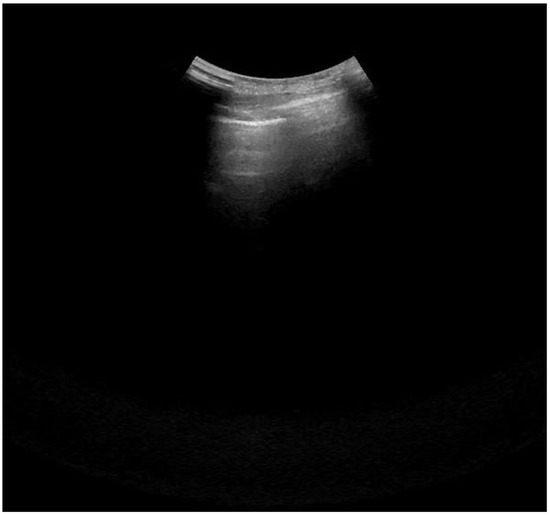

:1. Introduction

2.1. Study Design

2.4. Lung Ultrasonography and Score Assessment